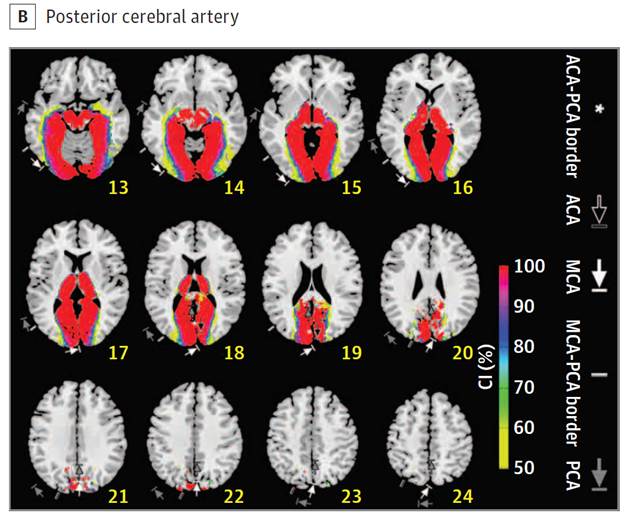

Posterior

circulation

Cerebral vascular territories